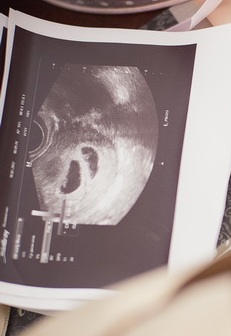

Муж ушел на работу, я еще собираюсь. Сделаю ка я еще один тест... две полоски))) Мужу нужно это как то сообщить, не хотелось бы как то банально. Загляну ка я в Инвитро у дома. УЗИ. "Ну знаете, пока я не вижу плодного яйца. Если тест показывает две полоски - беременность скоре всего есть, но срок еще очень маленький... Вот тут в центре есть малюсенькая точечка, может и оно... Приходите ка через пару недель". Мда... так долго ждать не хочу, придется рассказать мужу как есть, без точного подтверждения УЗИ. Вечер. Звоню. "Знаешь, так цветов хочется, подари мне пожалуйста мои любимые розы". Пока он еще не пришел достаю фотографию УЗИ с этой непонятной точкой в центре, тест с бантиком и бирочкой "Кажется, я уже у мамы в животе". Вот и муж, цветы... "А у меня тоже для тебя подарок - смотри..."

Накенец-то прошли эти недели, теперь уж можно делать УЗИ, надеюсь ничего не рассосалось))) Инвитро. Муж остался в машине.

"Ну давайте посмотрим. Так... А у вас беременность наступила естественным образом?" - "В каком смысле?" - "ЭКО не было?" ... "???, вы хотите сказать что он там не один??? у нас естественная беременность!!!" - "Да, не один. Я отчетливо вижу два плодных яйца. Вот послушайте их сердечки" Боже, у меня у родной сестры двойня, молния же два раза в одно место не бьет! ))) Чтобы убедиться, что врач не ошиблась, я аж соскочила с кушетки! Двойня, какое счастье!!! Таааак, это надо тоже как-то мужу сообщить...